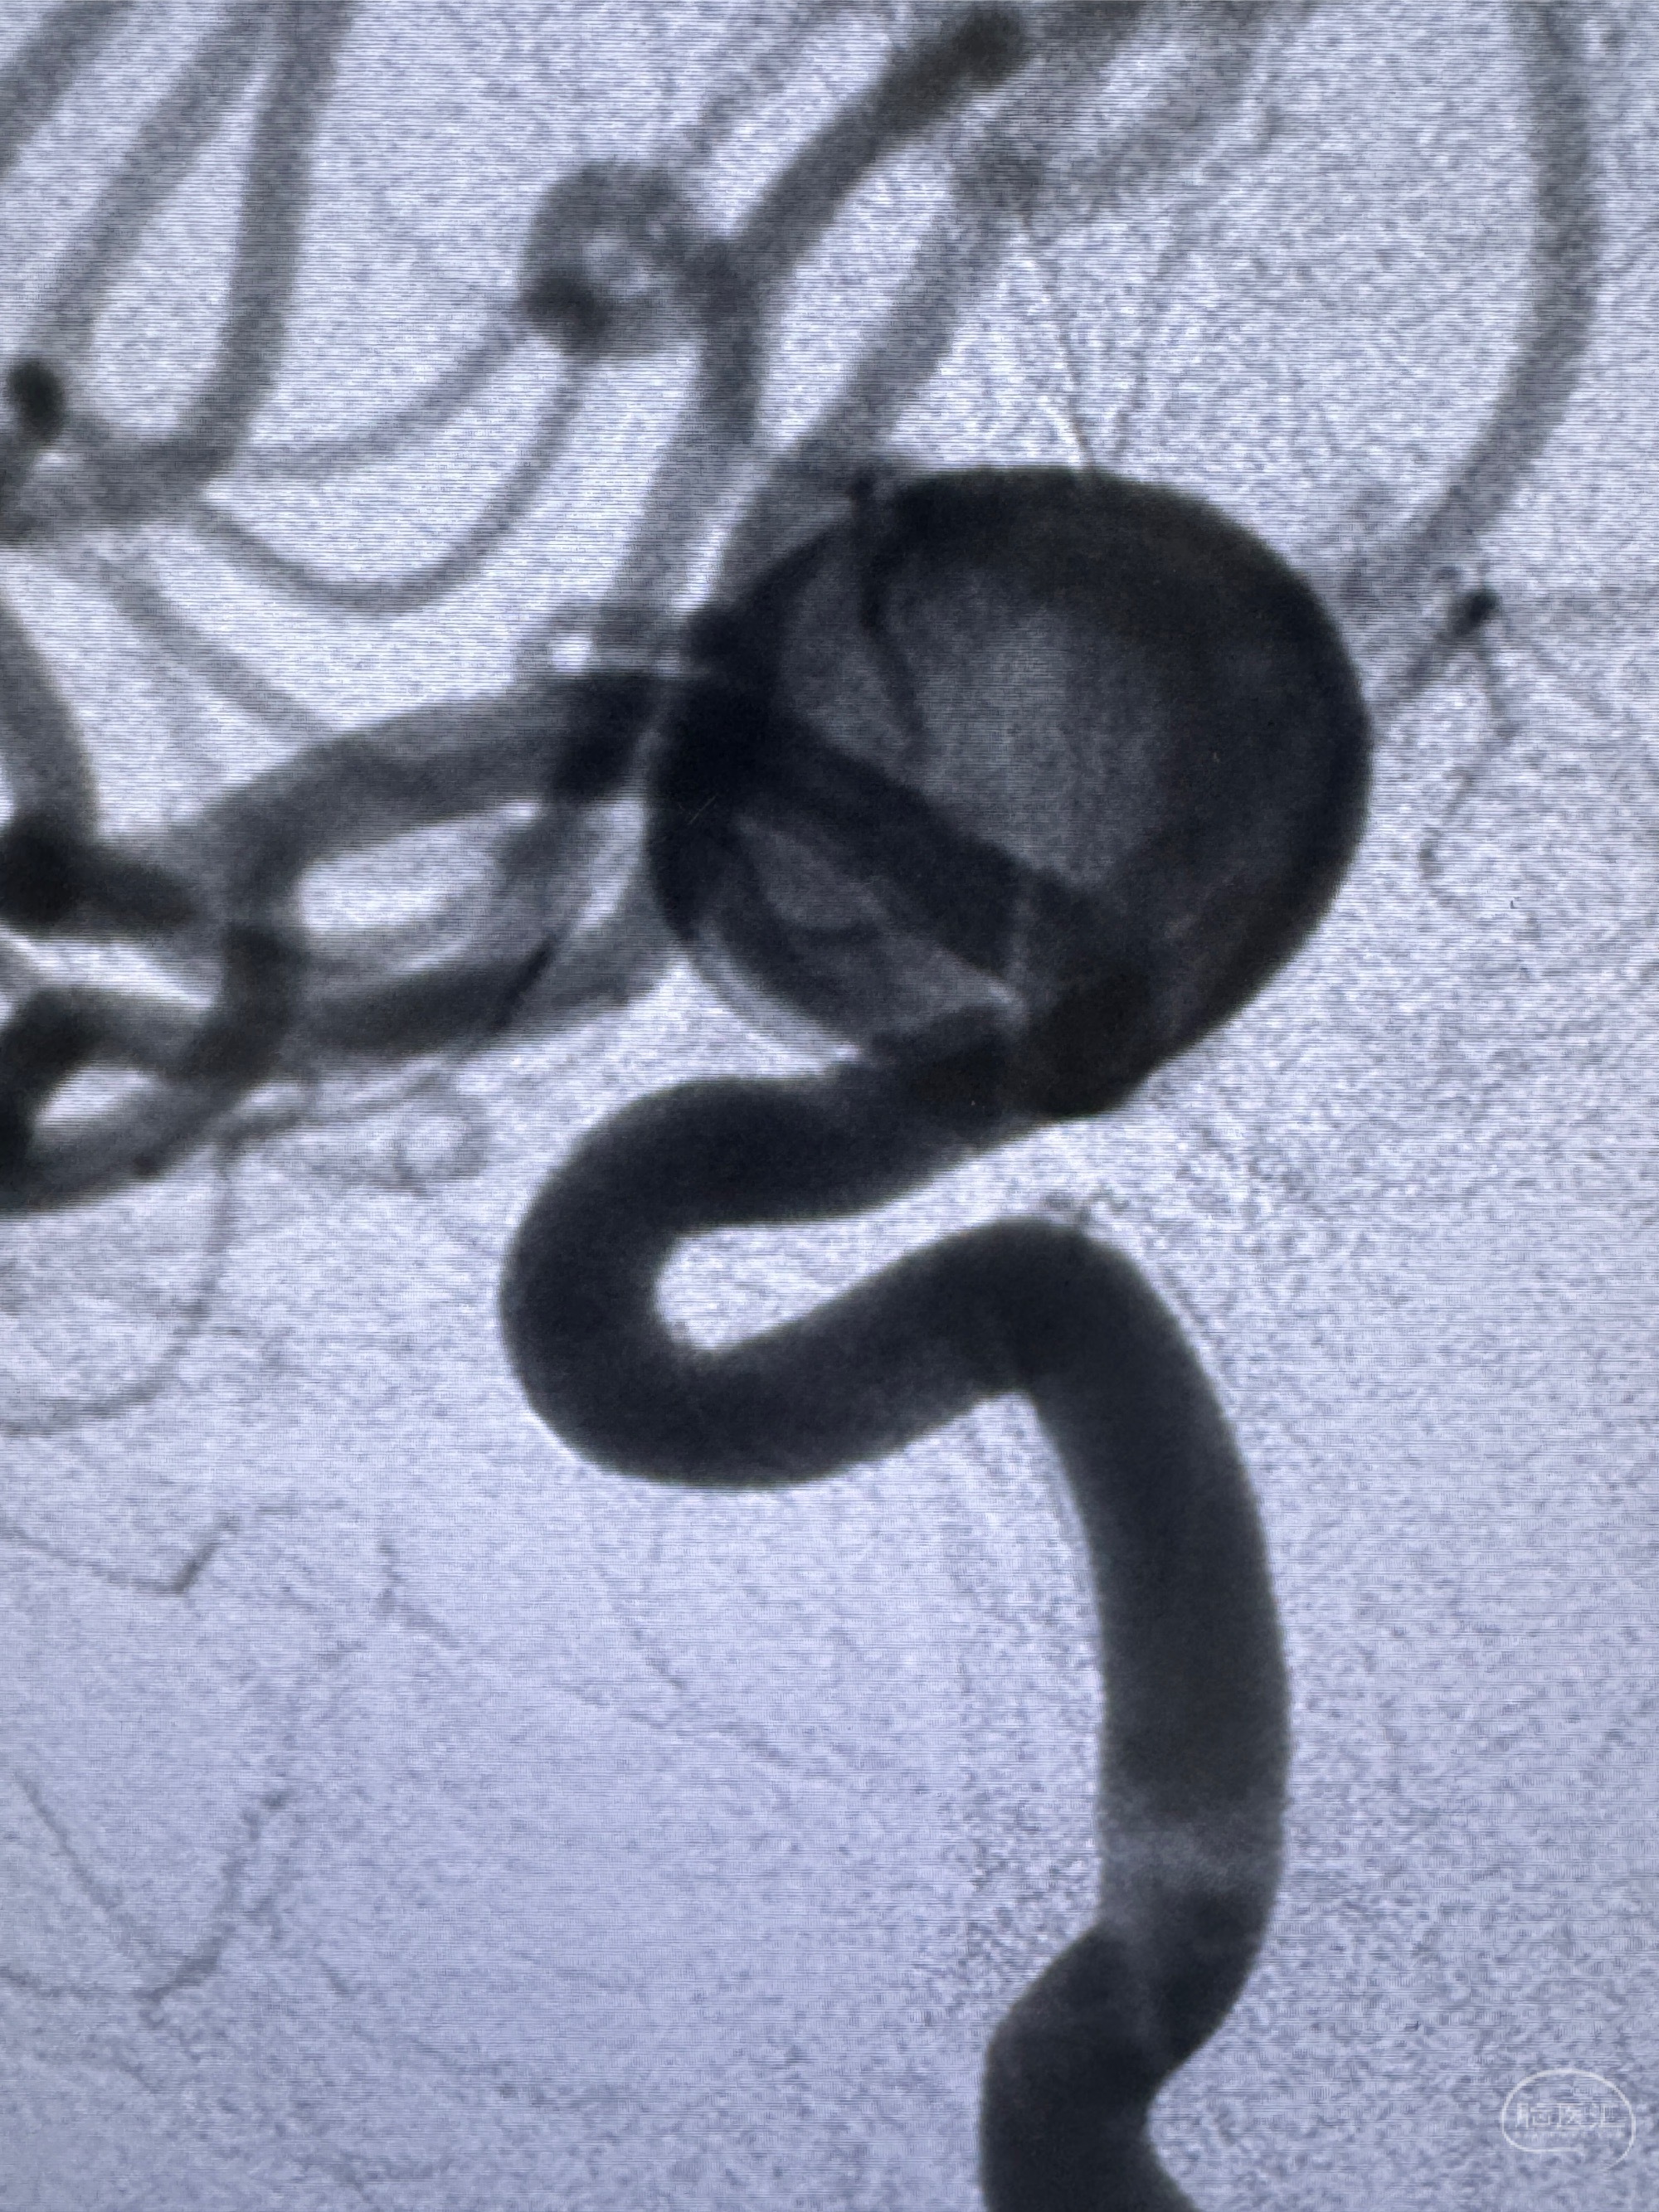

2023-12-27术后第十天复查DSA

支架贴壁佳,但可见射流,咋办?

2024-01-08全麻下再行植入密网支架一枚

Tubridge 4.5-35mm

支架植入顺利,贴壁佳,支架内血流通畅,动脉瘤内血液滞留明显